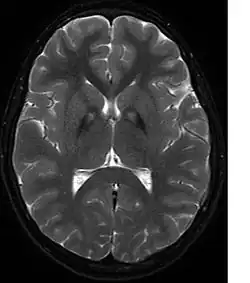

MRI image shows iron deposits in the basal ganglia, the so-called eye-of-the-tiger sign (T2w GRASE sequence).

A neurological examination would show evidence of muscle rigidity; weakness; and abnormal postures, movements, and tremors. If other family members are also affected, this may help determine the diagnosis. Genetic tests can confirm an abnormal gene causing the disease. However, this test is not yet widely available. Other movement disorders and diseases must be ruled out. Individuals exhibiting any of the above listed symptoms are often tested using MRI (Magnetic Resonance Imaging) for a number of neuro-related disorders. An MRI usually shows iron deposits in the basal ganglia. Development of diagnostic criteria continues in the hope of further separating PKAN from other forms of neurodegenerative diseases featuring NBIA.

Microscopic features of PKAN include high levels of iron in the globus pallidus and the pars reticulata of substantia nigra, evident as a characteristic rust-brown discoloration[7] in a pattern called the eye-of-the-tiger sign;[8] lipofuscin and neuromelanin concentrated in the iron-accumulating areas; oval, nonnucleated structures representing swollen axons whose cytoplasm swells with vacuoles, referred to as spheroids, axon schollen, or neuroaxonal dystrophy; and Lewy bodies.[7]